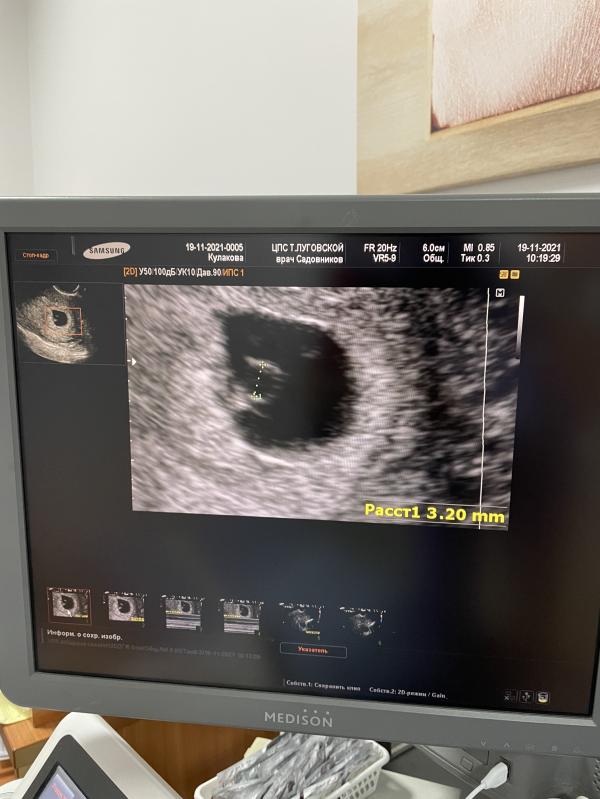

Первое фото малыша 💕 ходили сегодня на узи , сердечко уже слышно 💕 и видно эмбрион 🥰

Расти наш маленький ☺️